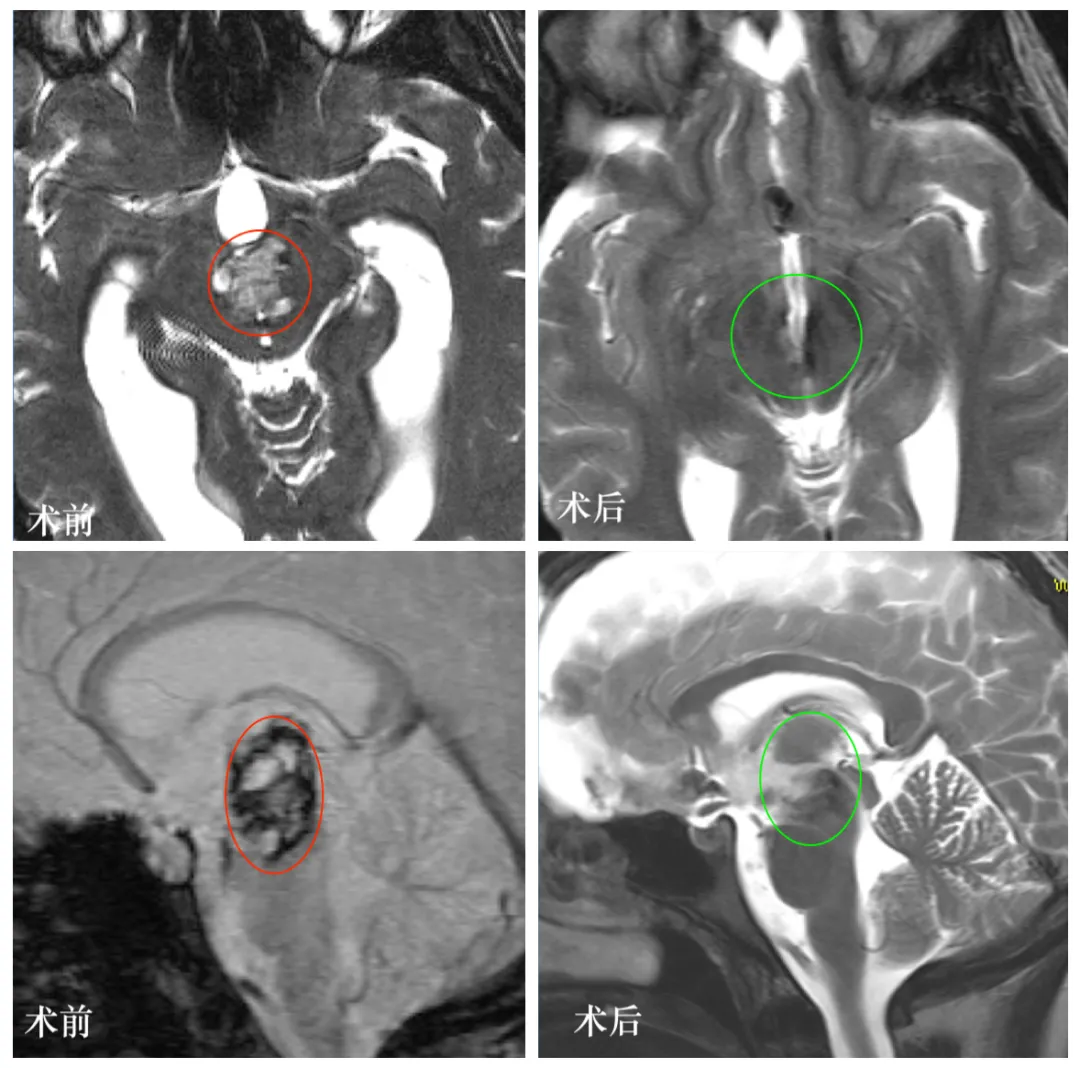

图:L同学颅脑MR显示中脑巨大占位,混杂信号,海绵状血管瘤可能。

图:手术前后颅脑MR对比,术后MR中脑脑干病变全切,无脑组织损伤等。

术后第2天:复查CT显示正常,病变全切,转至普通病房;

术后2年:Lily已完成学业,取得本科学位,工作、生活一切正常。复查MRI显示病变全切,无复发,无任何神经功能损伤。